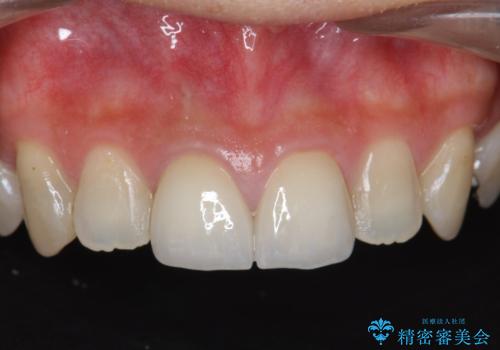

[ オールセラミッククラウン ] 前歯を自然な差し歯にしたい

![[ オールセラミッククラウン ] 前歯を自然な差し歯にしたいの症例 治療前](https://seimitsushinbi.jp/wp/wp-content/uploads/2022/07/3c5a785637ddccbb5d7fcd0b4a151157-500x350.jpg?v=1657095795)

![[ オールセラミッククラウン ] 前歯を自然な差し歯にしたいの症例 治療後](https://seimitsushinbi.jp/wp/wp-content/uploads/2022/07/f908365bae813c6881b43ba51882c130-1-500x350.jpg?v=1657095942)